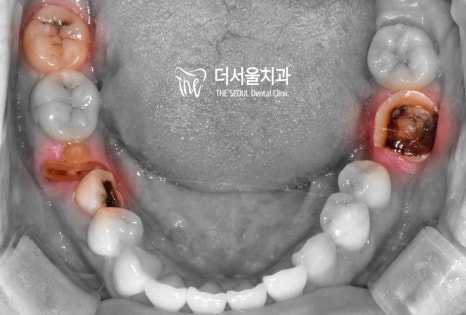

상, 하악 초진 사진입니다.

한눈에 봐도 썩은 곳들이 많네요.

그중에서는 더는 자연치를 살릴 수 없을 정도로

심각한 상태인 치아들이 많았는데요.

위 사진에서 볼 수 있듯이

약간 뻐드러진 치아 배열과 우식,

그리고 제위치에서 벗어난 소구치 때문에

여러 고민이 많으셨던 분인데요.

이분께서는 교정과 우식 제거를

동시에 원하고 계셨던 상태였습니다.

따라서 더 서울에서는 충치치료 먼저 진행한 뒤,

치열 개선을 시작하는 방법으로 돕기로 했는데요.